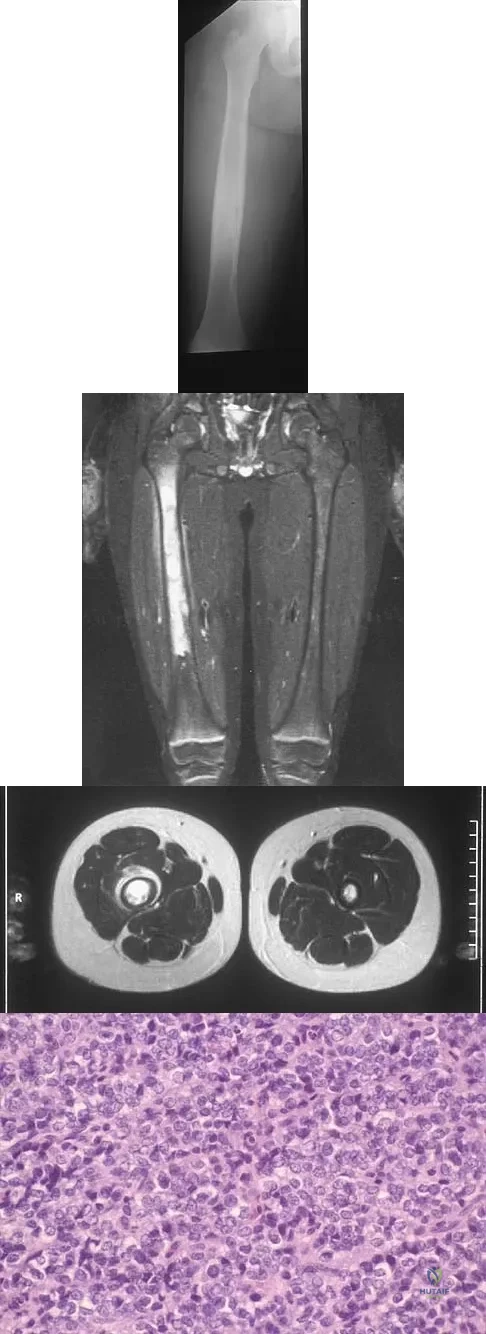

A radiograph, MRI scans, and a biopsy specimen of a 9-year-old boy with thigh pain are shown in Figures 37a through 37d. Management should consist of

Explanation